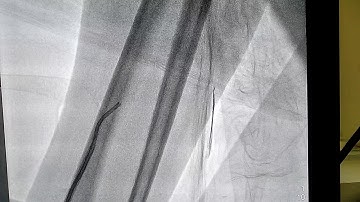

Radial artery loop: management